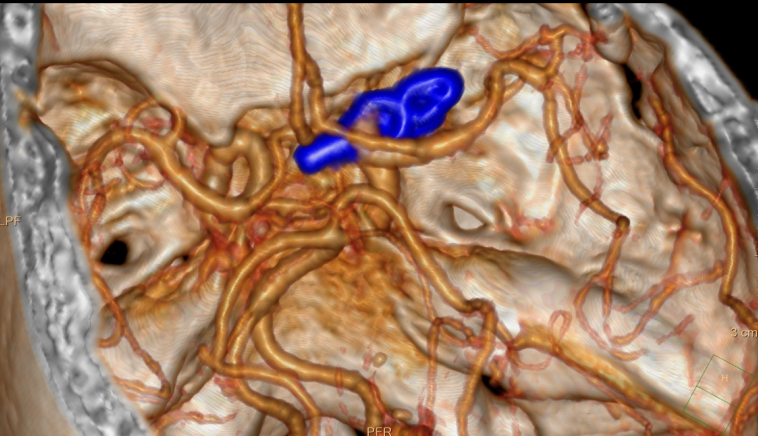

颅内动脉瘤就像脑血管壁上吹起的 「小气球」,血流冲击下会不断变大,一旦破裂就会引发蛛网膜下腔出血,致死致残率高达 70% 以上,被称为 「颅内炸弹」。更让人揪心的是,进一步 DSA 检查发现,这颗 「炸弹」 还是分叶状的,这些分叶如同瘤体长出的 「小尾巴」,形态不规则且边界参差不齐,破裂风险极高;而左侧同一位置,竟然还有一颗 「镜像动脉瘤」。

经过综合评估,并与患者及家属充分沟通后,汤主任决定施行脑动脉瘤夹闭术,本次手术优先处理右侧的高风险动脉瘤,左侧的动脉瘤择期处理。

6 月 5 日,手术室成了没有硝烟的战场。前床突,这个深藏于颅底的楔形骨质结构,虽仅有指甲盖大小,却像一道天然屏障,牢牢遮挡着颈内动脉腹侧的动脉瘤。主刀医生必须如同「拆弹专家」 般,精准移开这道阻碍。术中,汤主任采用 「钥匙孔」 入路:以微小的切口,打开颅骨,切开硬膜后,精准磨除前床突,小心分离周围组织,一点点暴露眼动脉和动脉瘤。

血管壁比纸还薄,稍微一碰就可能破裂。术中,显微镜下的操作堪比「绣花」:特制钛合金动脉瘤夹必须精准卡在瘤颈处,既要彻底阻断瘤体血流,又不能影响正常血管供血。当夹子稳稳闭合的瞬间,团队成员才敢喘口气 —— 这颗高风险动脉瘤,被成功 「拆除」。

术后 CTA 显示:动脉瘤完全消失,血管通畅无阻。这场毫米级的生命保卫战,赢了!